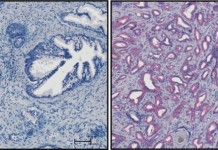

Воздействие на одну-единственную молекулу может решить проблему рака простаты

В распространении рака простаты участвует одна определенная молекула, которая критически важна для этого процесса. Названная учёными SRPK1, это образование позволяет оп...